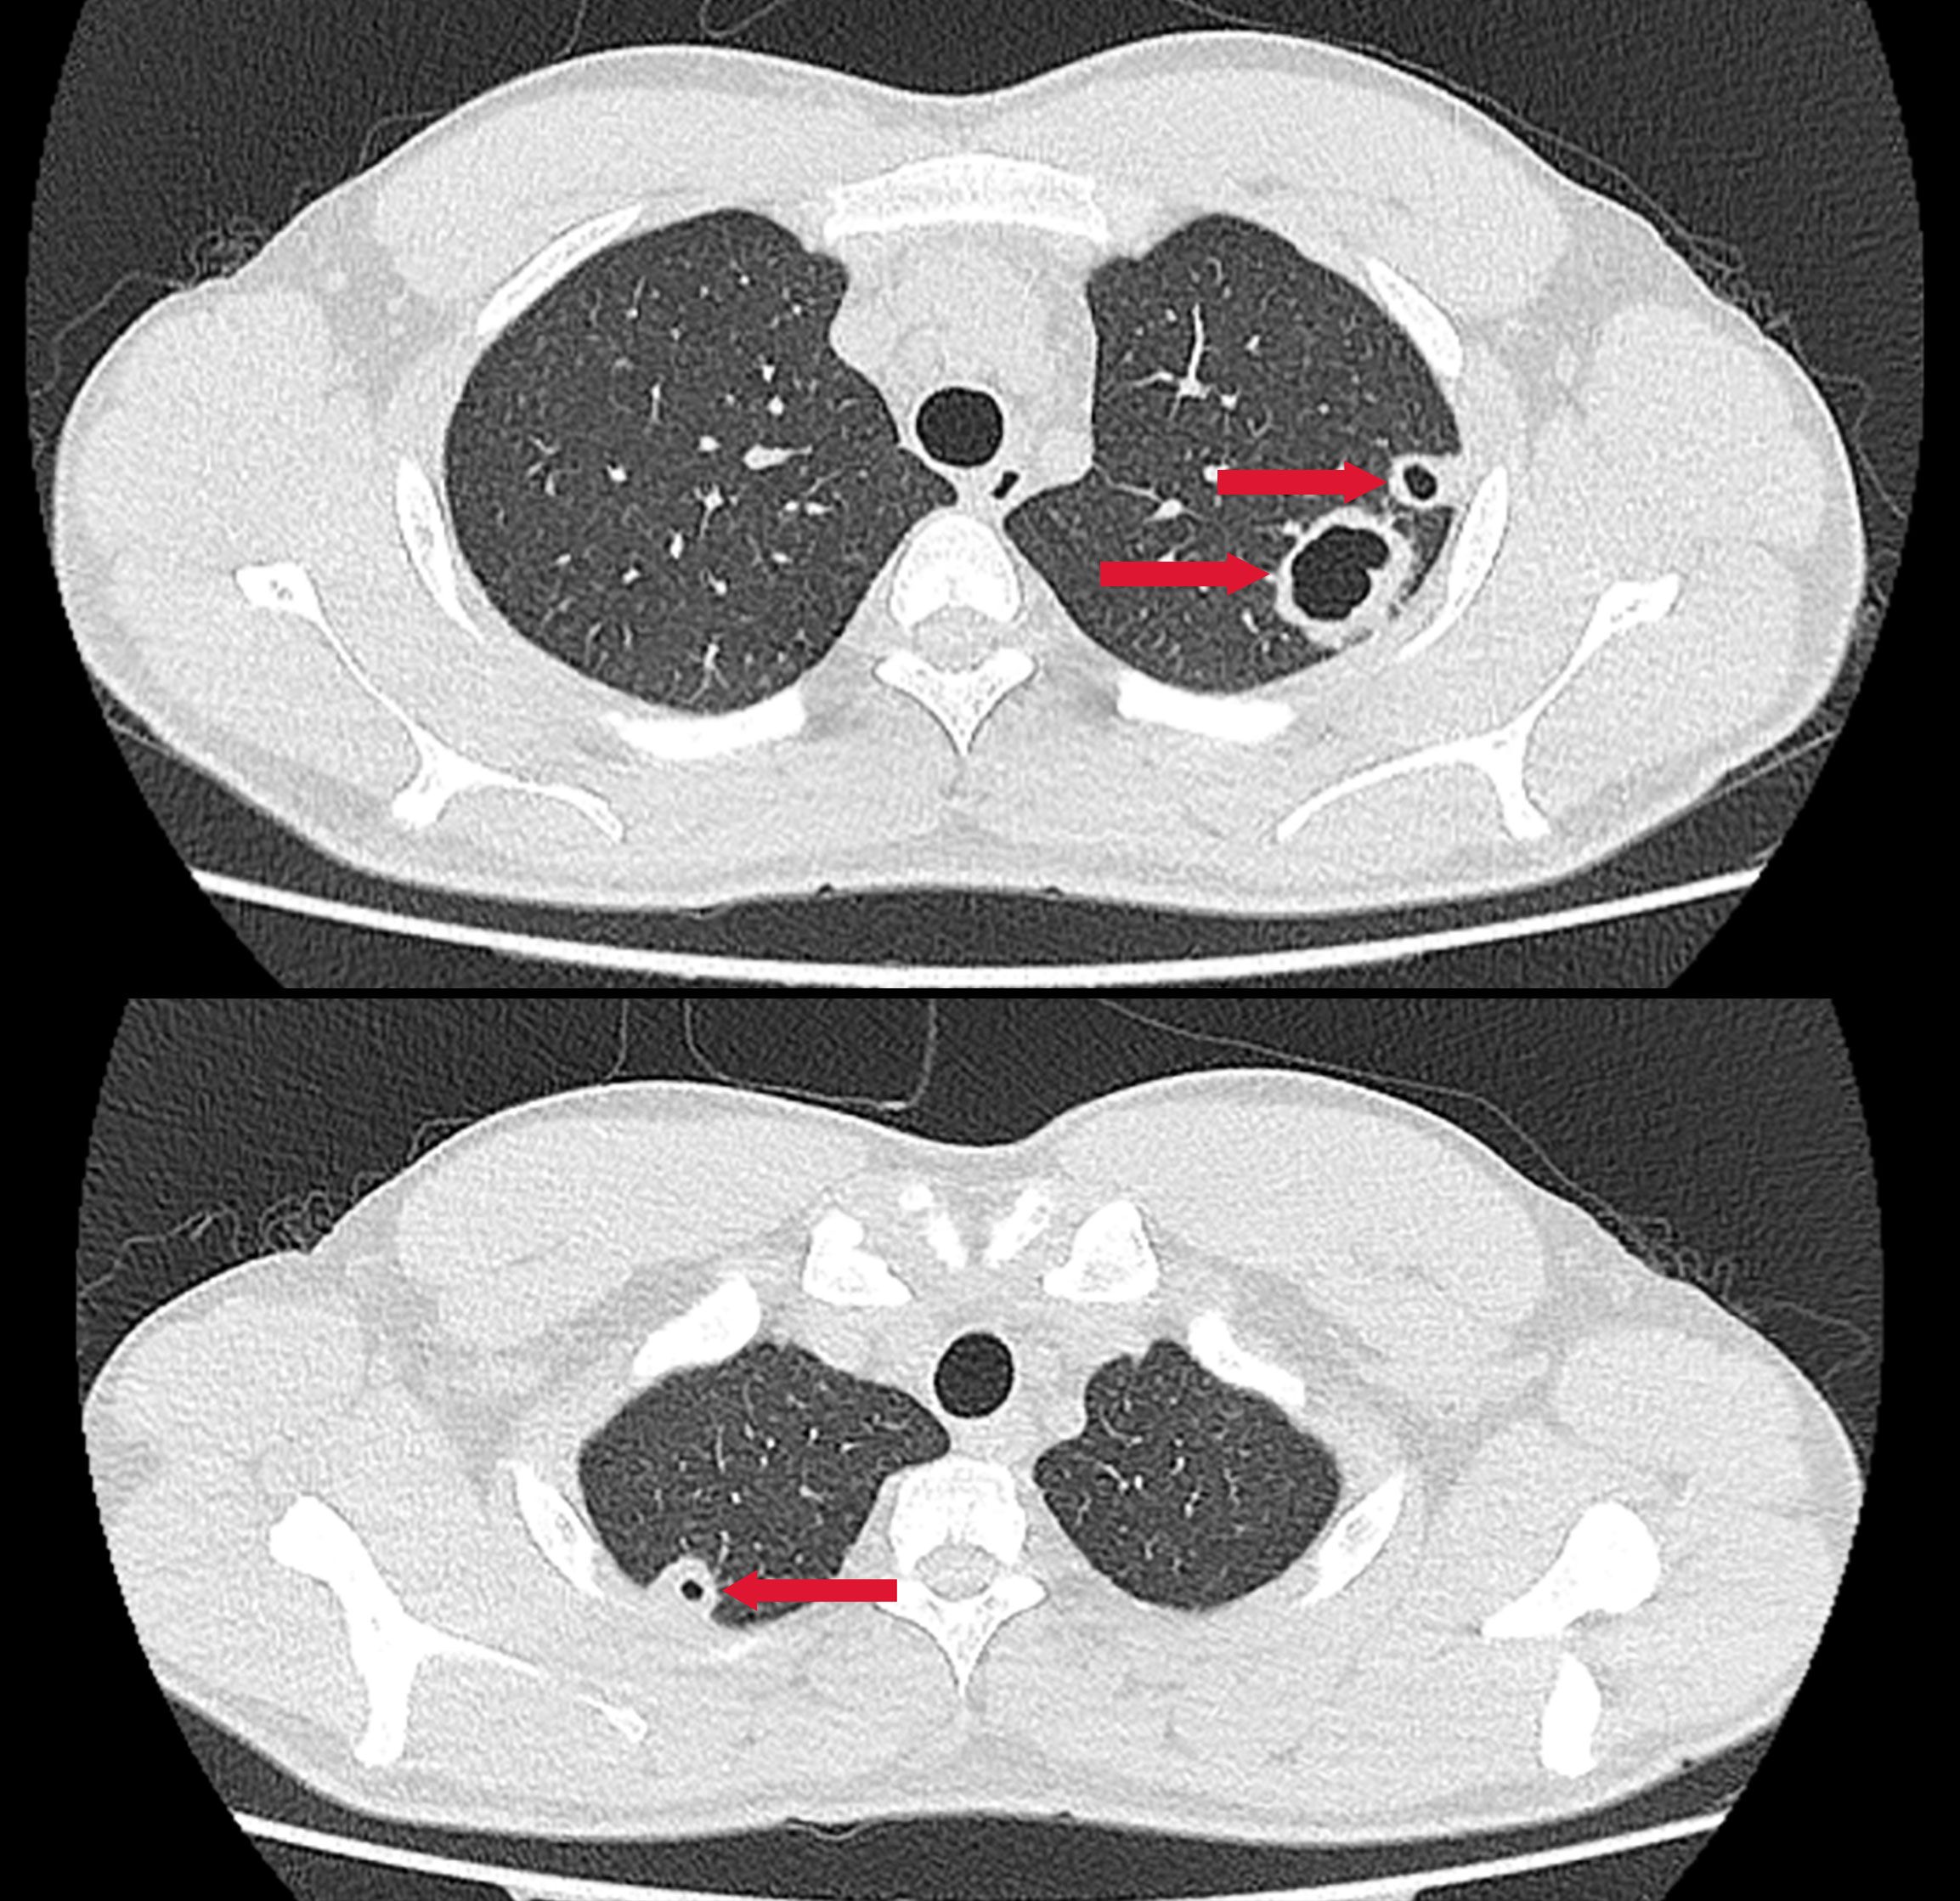

A previously healthy 25-year-old male developed high fever (maximum 40°C) without an identifiable cause while traveling in Jiangxi, China. The fever was accompanied by mild cough and sputum production. Despite self-medicating with over-the-counter cold medication, his symptoms persisted. Five days later, he experienced sudden onset of blurred vision, redness, and painful swelling in his left eye. After nearly a week of persistent symptoms without improvement, he underwent a chest CT scan, which revealed a pulmonary mass, prompting further evaluation. Upon hospital admission on August 2, 2024, CT imaging demonstrated multiple pulmonary nodules with partial cavitation, suggesting a possible infectious etiology (Figure 1). Orbital CT revealed an intraocular mass in the left eye, with irregular margins of the left globe and heterogeneous attenuation in the peribulbar and orbital apex tissues (Figure 2). Additionally, a low-density hepatic lesion was identified (Figure 3), raising suspicion of a liver abscess, and a low-density nodule was detected in the right thyroid lobe. Laboratory tests revealed leukocytosis and significantly elevated inflammatory markers, leading to the initiation of empiric antibiotic therapy with ceftriaxone sodium. Two sets of peripheral blood cultures collected on August 4, 2024 (left and right upper limbs) were negative; blood cultures were not repeated. Due to patient non-cooperation, a complete ophthalmologic evaluation of the left eye was not feasible. Hemodynamics remained stable without vasopressors (SBP 110–130 mmHg/DBP 70–85 mmHg); lactate was 1.2 mmol/L, urine output was ≥1 mL/kg/h, and mental status was normal, indicating no clinical evidence of septic shock. On August 5, 2024, bronchoalveolar lavage fluid (BALF) culture grew K. pneumoniae without detected antimicrobial resistance. Metagenomic next-generation sequencing (mNGS) of bronchoalveolar lavage (BAL) fluid further confirmed the presence of K. pneumoniae. Given the severity of the infection, the antimicrobial regimen was escalated to meropenem. Despite intensive antimicrobial therapy, the infection progressed rapidly, affecting multiple organ systems. The patient was diagnosed with invasive K. pneumoniae syndrome, characterized by pulmonary abscess, liver abscess, thyroid nodule, and endogenous endophthalmitis with retinal detachment. Given the disseminated nature of the infection, the antimicrobial regimen was further adjusted to meropenem plus levofloxacin. Although systemic infection was gradually controlled, the left eye infection continued to deteriorate. The patient developed worsening ocular pain and progressive vision loss. Ophthalmologic evaluation revealed scleral ulcer perforation with extensive orbital tissue necrosis, resulting in irreversible ocular damage. Due to the severity of the infection, on August 21, 2024, the patient underwent left ocular enucleation. Postoperative ocular tissue cultures confirmed K. pneumoniae infection. Following surgery, the antimicrobial regimen was adjusted from meropenem plus levofloxacin to cefoperazone-sulbactam. By the time of discharge, follow-up imaging demonstrated a reduction in pulmonary and hepatic abscess size, with adequate infection control. Figure 4 illustrates the detailed course of disease progression.

Figure 1. Chest CT showing multiple nodular and patchy high-density opacities in both lungs with ill-defined margins. Several lesions exhibit cavitation. Red arrows indicate the lesion areas.